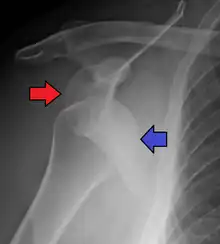

Posterior (backward)

Posterior dislocations are uncommon, and are typically due to the muscle contraction from electric shock or seizure.[5] They may be caused by strength imbalance of the rotator cuff muscles. People with dislocated shoulders typically present holding their arm internally rotated and adducted, and exhibiting flattening of the anterior shoulder with a prominent coracoid process.

Posterior dislocations may go unrecognized, especially in an elderly person[11] and in people who are in the state of unconscious trauma.[12] An average interval of 1 year was noted between injury and diagnosis in a series of 40 people.[13]

Lightbulb sign indicative of posterior shoulder dislocation shown on the left. On the right, the same shoulder after reduction. -

Axillary view of the left shoulder showing a posterior dislocation